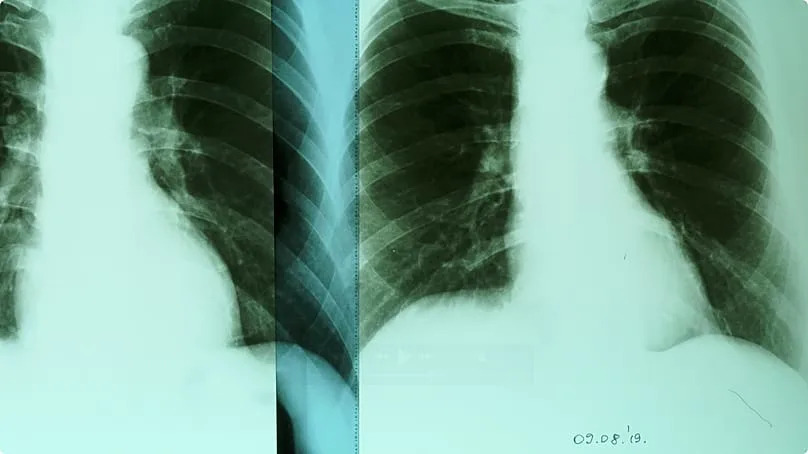

The residents are afraid of poisonous vegetables, deadly air and cancer. But is all of this true? At the hospital in Kakanj, I meet an expert on respiratory diseases. Senka Balorda is one of the most renowned doctors in Bosnia and Herzegovina.

“Yes, we do have a problem in Kakanj”, Senka Balorda confirms. “I think that as reported for 2025, for the 35.000 citizens of Kakanj, we have 223 different cancer patients. That’s really huge.”

Euronews: “What is the connection between coal and the diseases?”

Senka Balorda: “The particle that we breath in goes through the trachea, the great bronchus to small bronchus, and at the end to the small, farthest paths of the smallest alveoli in the lungs.”

“Air pollution is a direct cause of lung cancer”, says Senka Balorda. – Hans von der Brelie

Euronews: “Can air pollution kill?”

Balorda: “Of course, because in this period large numbers of lung cancers have been discovered. I have sent seven of my patients to Tešanj hospital. All those seven patients have died. The air pollution is a direct cause of lung cancer.”

European Environment Agency and World Bank warn: High levels of air pollution in Bosnia and Herzegovina is responsible for over 3,000 premature deaths each year. When adjusted for population size, this is a European record.